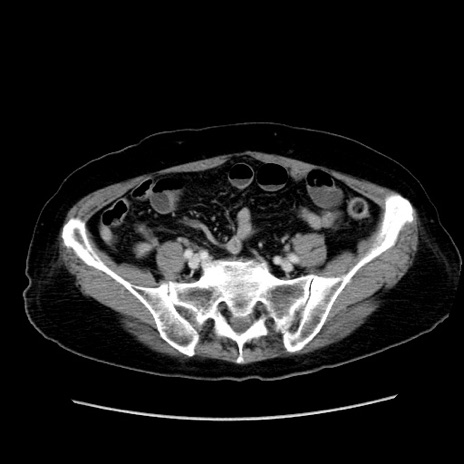

症例19(横断像)

【症例】80歳代女性

【主訴】下腹部痛

【現病歴】約8時間前より下腹部痛の出現あり、救急外来受診。

【既往歴】両側付属器切除

【身体所見】意識清明、下腹部正中に手術痕あり、その部位に一致して圧痛と反跳痛あり。腸蠕動音は亢進。

【データ】WBC 9300、CRP 0.15